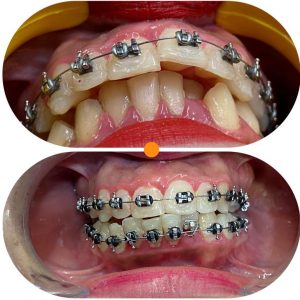

Tratamientos Ortodoncia Blanqueamiento dental Zoom Contacto 72 2795 9597 Marcar Ahora Envia whatsapp Visita nuestro facebook